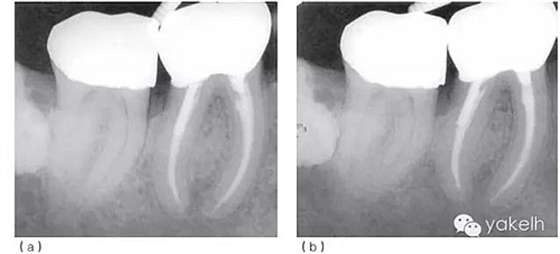

術(shù)后觀察愈合情況。最后制作新的樁冠。術(shù)后2年、6年復(fù)查,X線片顯示根尖周病損逐漸恢復(fù)(圖5.1.3)。

圖 5.1.3(a)根管再治療后2年復(fù)查,X線片顯示46根尖周骨重建、遠(yuǎn)中根管內(nèi)金屬樁、金合金冠修復(fù)。(b)根管再治療后6年復(fù)查,X線片顯示46根尖周完全恢復(fù)。